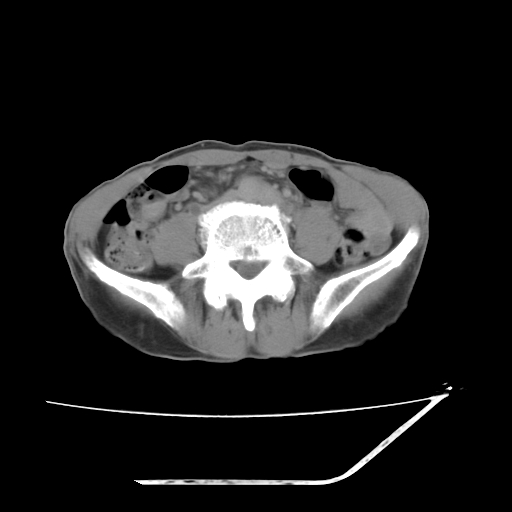

考虑右肾盂癌,肾动脉受侵,右肾功能减退,右肾盂输尿管积水,管壁增厚,考虑种植转移,应该把下面扫完的

考虑右侧肾盂癌。右侧输尿管扩张未扫描完。

右肾盂癌,肾动脉受侵,右肾盂输尿管积水,管壁增厚,考虑种植转移

右肾盂移行细胞癌并右输尿管中段转移.肾积水.

3.右侧上段输尿管扩张,原因:(1)积水所致;(2)种植。